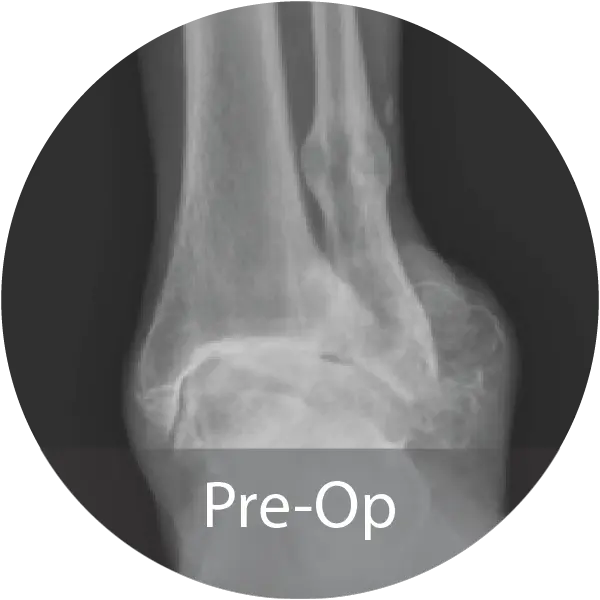

Case of 64-year-old female with hindfoot arthritis treated with tibiotalocalcaneal arthrodesis and intramedullary nailing using InduceXT®. Reported solid osseous consolidation with no postoperative complications, pain-free ambulation, and full return to activities.